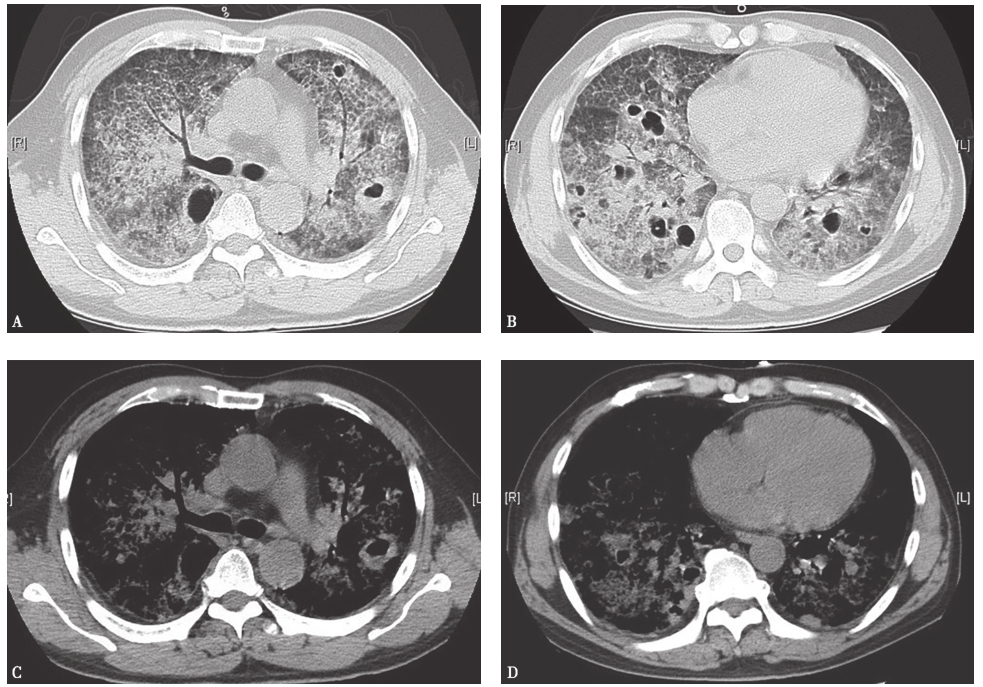

胸部HRCT:双肺弥漫性病变伴广泛多发空洞形成(图8),考虑为间质性肺疾病变合并感染(霉菌等特殊感染)可能性大。

图8复查胸部HRCT(2013-04-01)

胸部HRCT可见双肺弥漫病变较前加重,且出现双肺多发空洞样改变

图12治疗半个月后复查胸部CT表现

胸部CT示双肺弥漫病变较前吸收

图13治疗1个月后复查胸部CT表现

胸部CT示双肺病变继续吸收,空洞样改变有所吸收

图14治疗3个月后复查胸部CT表现

胸部CT示双肺病变基本吸收,空洞样改变遗留少许纤维条索和结节

图15治疗5个月后复查胸部CT表现

胸部CT示双肺病变及空洞基本吸收,遗留少许条索状纤维影